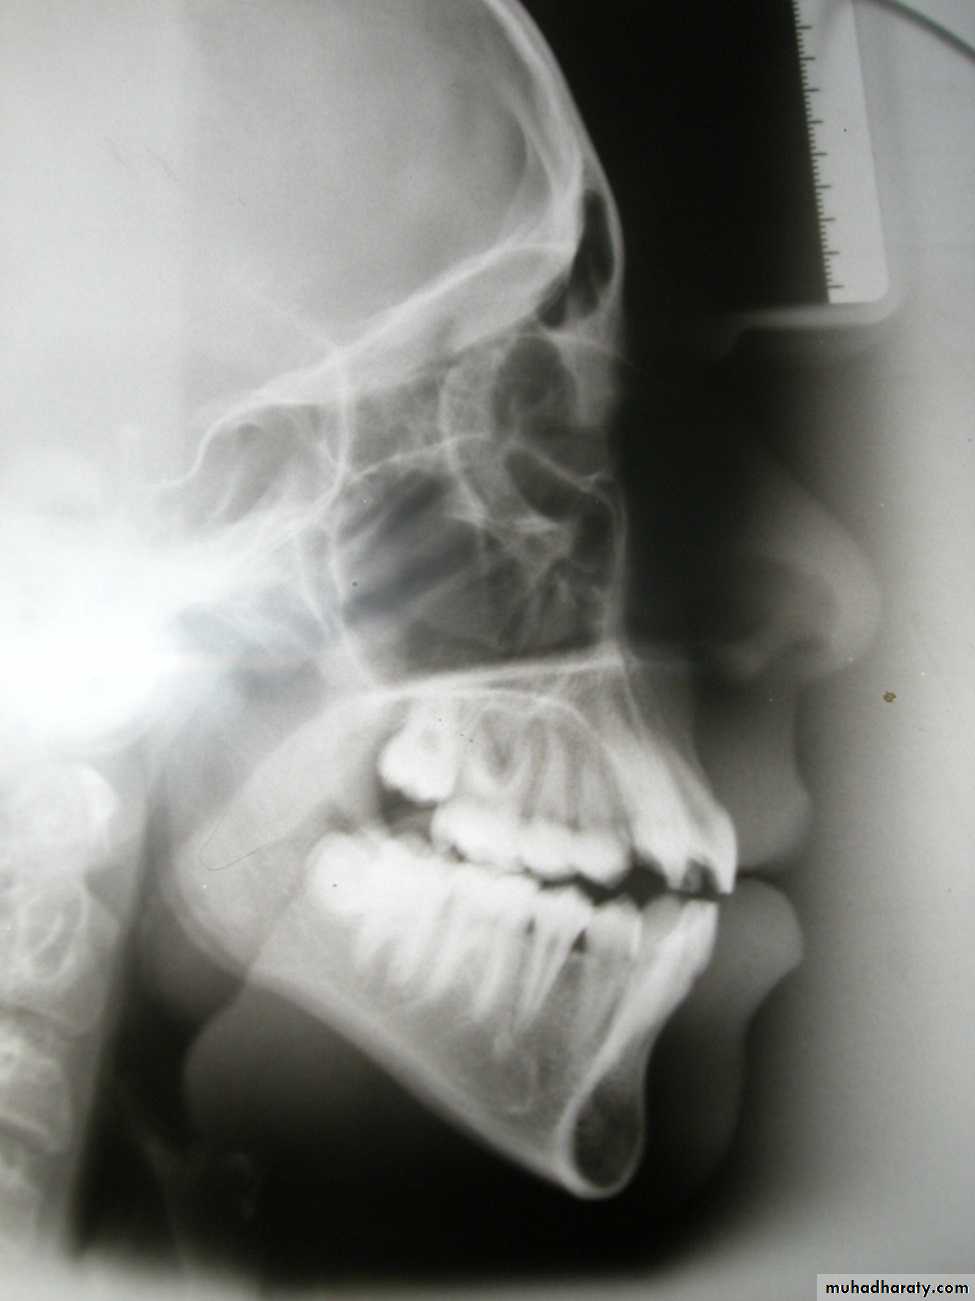

Dentoskeletal relationsUI / Mx plane angle (108 + 5)

LI / Mn plane angle (90 + 3)

Interincisal angle (133 + 10)LI / A-Pog distance (0 + 2 mm)

UI / Mx plane angle (108 + 5)

Dental Assessment

108

90

Incisor Angulation Assessment

Dental AssessmentL1-GoGn (Man 1 - GoGn)0 mm ± 2

Dental AssessmentAPog - Man 1130